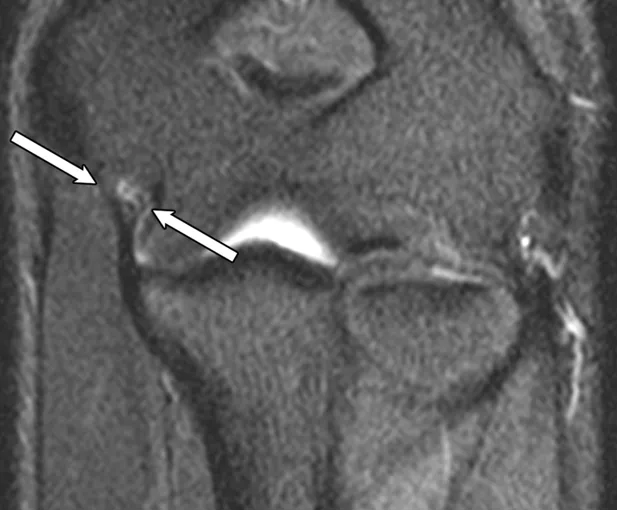

标注 A(冠状面脂肪抑制 T1 加权直接 MR 关节造影像)、B-D(轴面 T1 加权直接 MR 关节造影像):

• A 图:骨软骨损伤(白色箭头)和外侧尺侧副韧带全层撕裂(黄色箭头)

• B 图:后外侧滑膜皱襞(箭头)

• C 图:关节内游离体(箭头)

• D 图:全层软骨缺损(箭头)